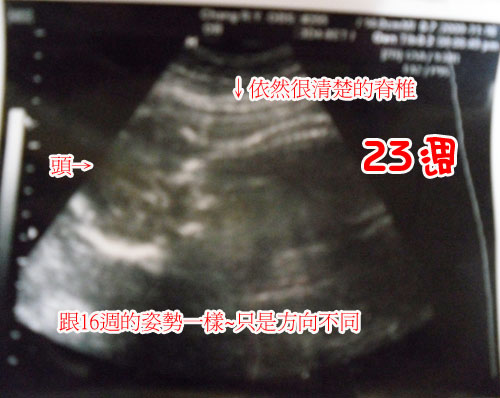

23週的產檢~照片有點模糊~因為寶寶是趴著的,